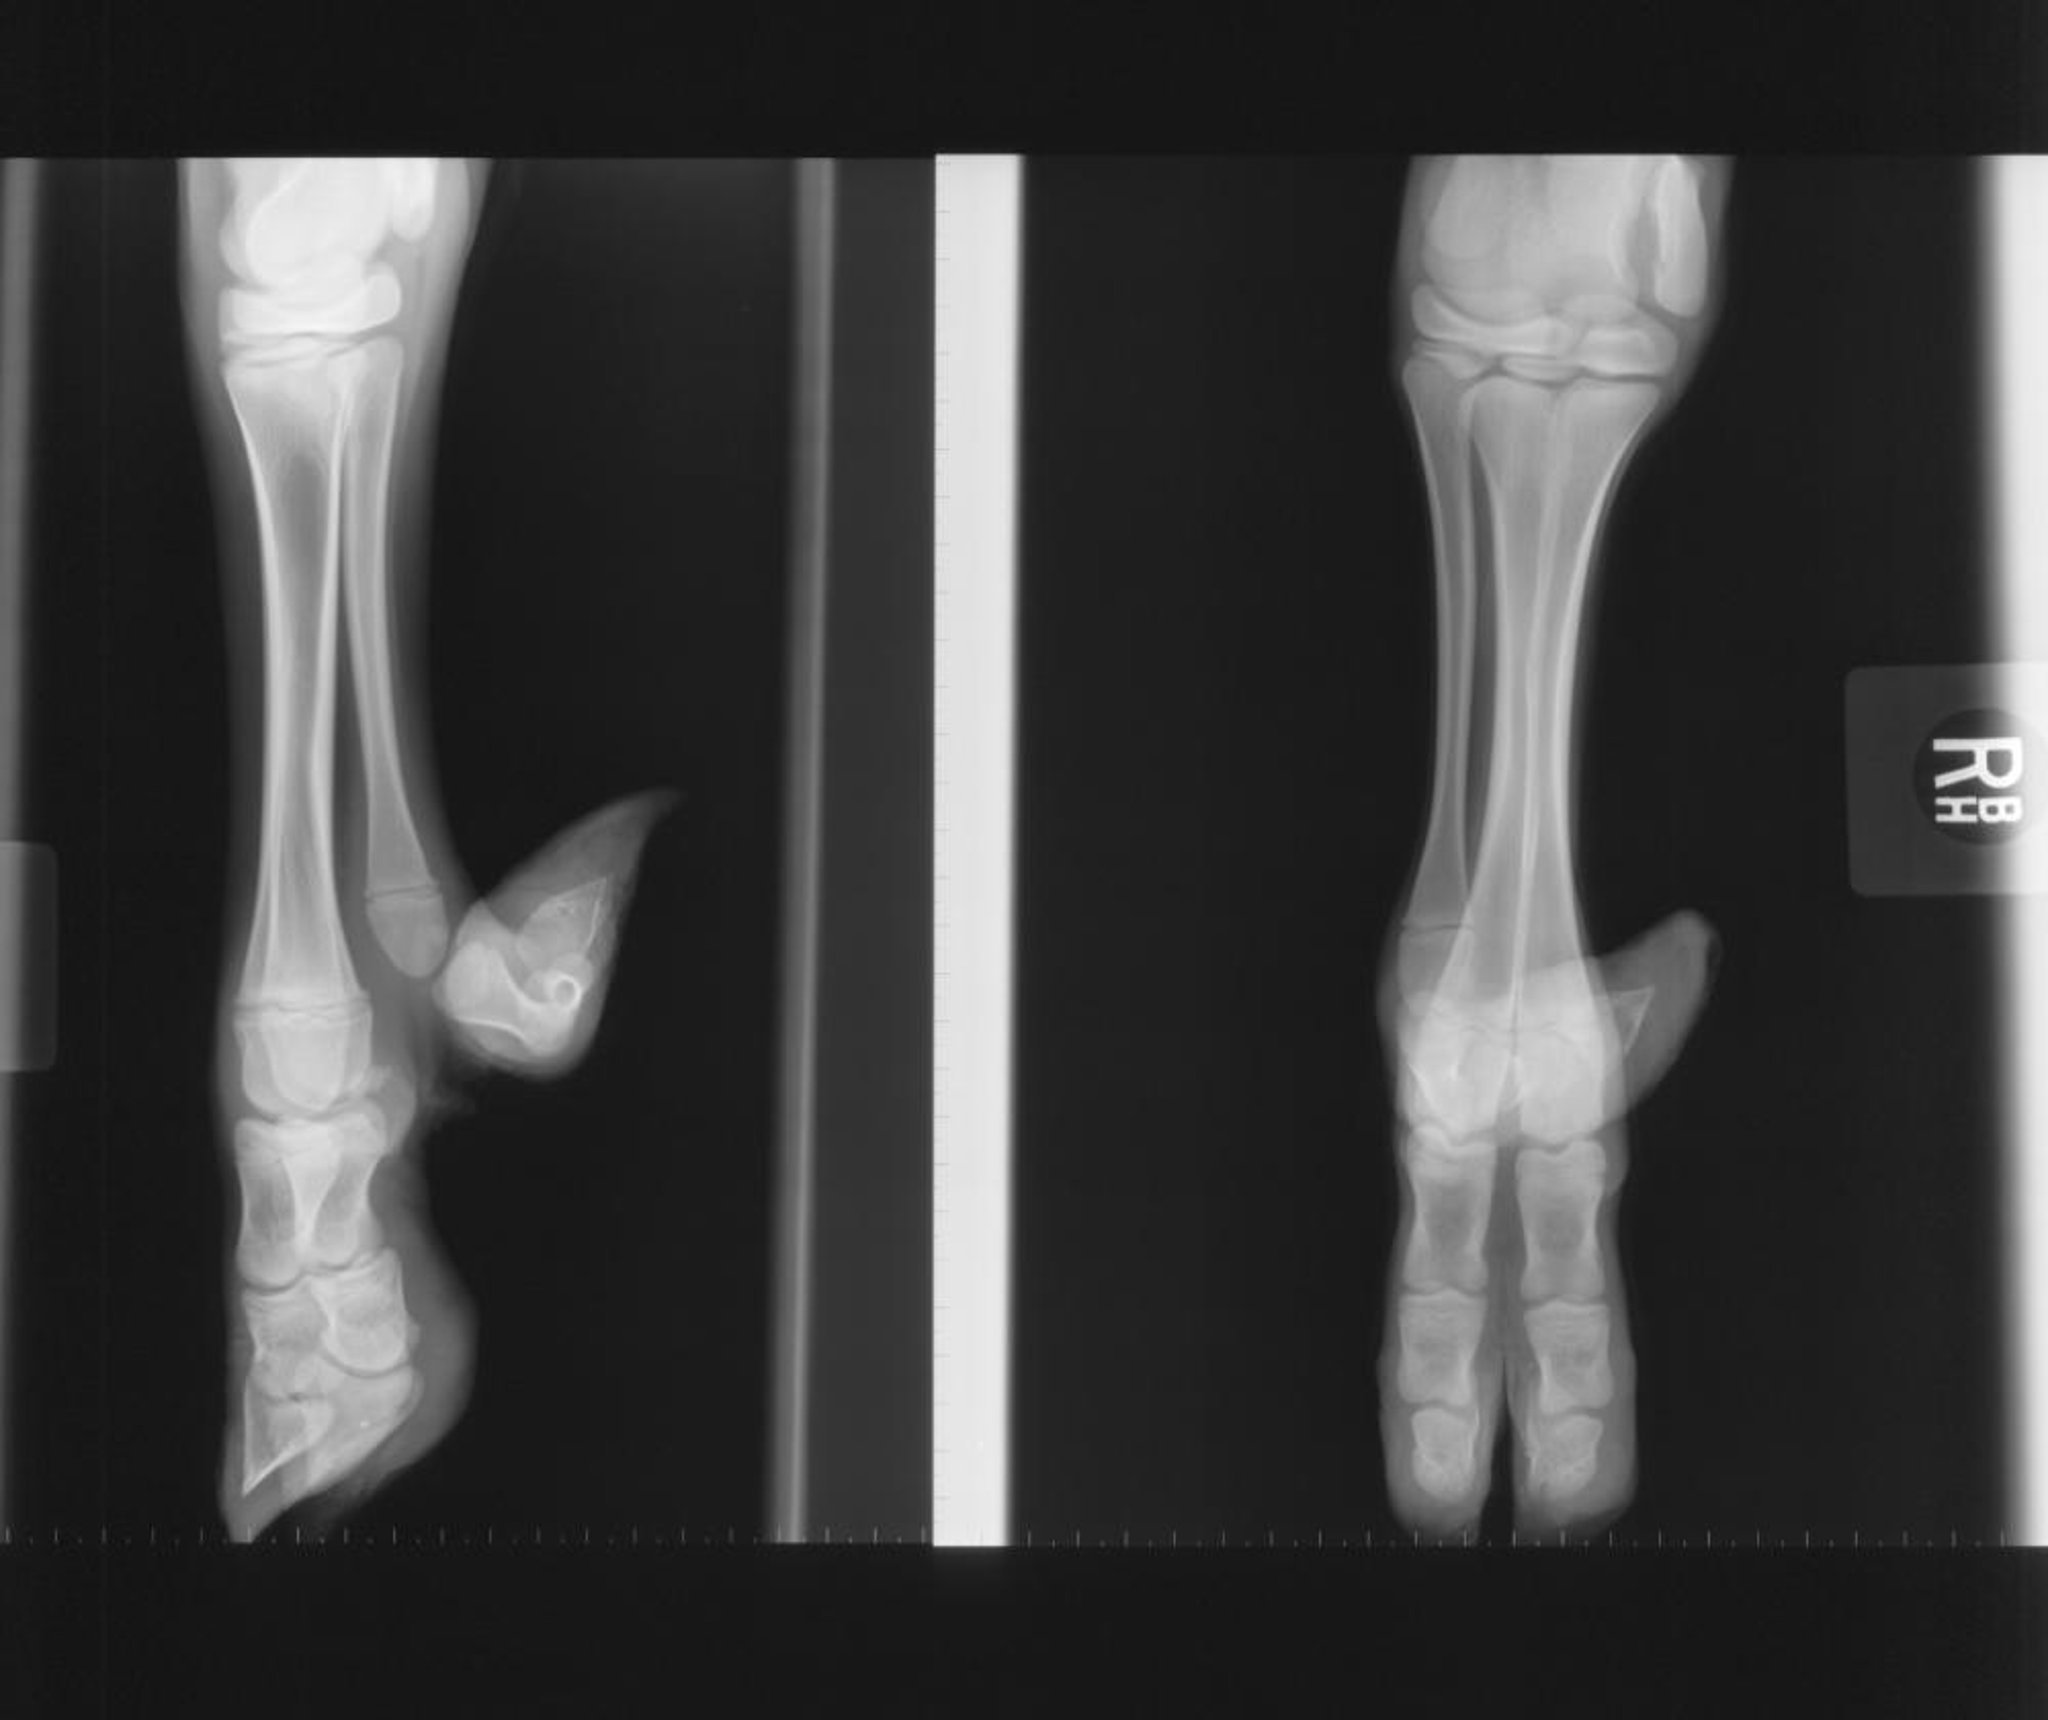

Polidactilia, radiografía, ternero

Radiografía de polidactilia en un ternero.

Cortesía de Robert Cole, DVM, DACVR.